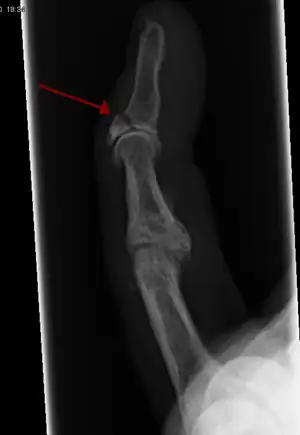

Internal and external views of an arm with a compound fracture, both before and after surgery

In the fingertip. More images